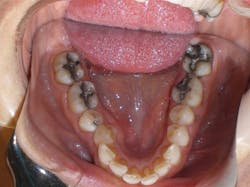

Case 3: 17-year-old male: 1-year treatment. Expanding and proclining delivered more room for the tongue and increased oral cavity volume without IPR or extractions. Case and photos courtesy of Dr. Ben Miraglia.

Before: V- and omega-shaped arch, crossbite. After: U-shaped arch, no IPR, no EXT, increased oral cavity volume.